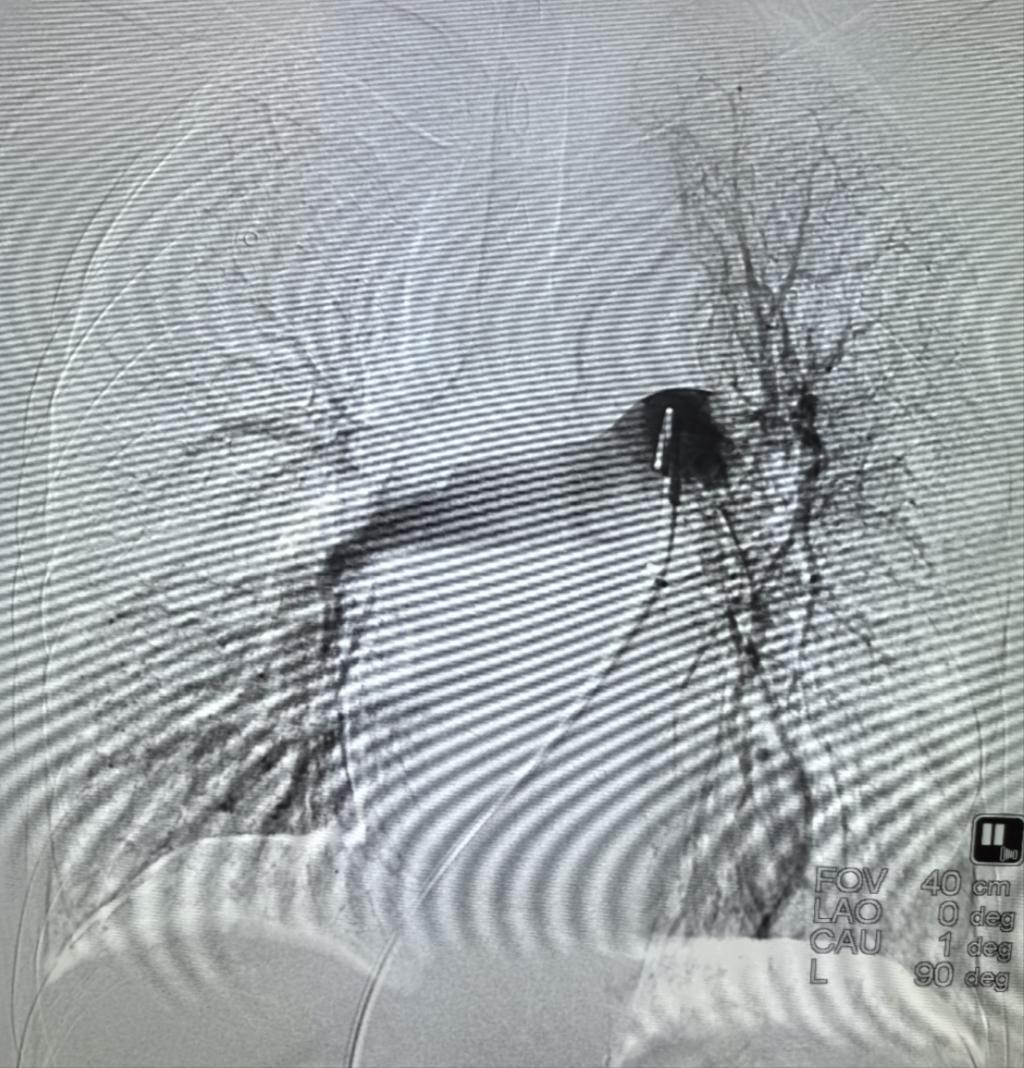

患者入院时,门诊CTPA提示:双肺动脉主干肺栓塞,伴有右心房栓子(性质不确定)、下肢深静脉血栓,经急诊抢救室初步评估为肺栓塞(高危)立即收住EICU。急诊科裴红红主任立即组织EICU李萍教授、急诊科介入团队彭卓副主任、古长维副教授评估患者后,决定给予患者行经导管肺动脉机械取栓术,这样不仅能够抽吸肺动脉栓子,同时能够明确右心房及肺动脉栓子性质。在影像科积极协助下,术中下腔静脉造影见下腔静脉血栓附着,通过精准定位行下腔静脉滤器置入。然后,肺动脉造影,见双肺显影不佳,左肺为著,测肺动脉压50mmHg,行肺动脉血栓抽吸术,术中明确栓子性质为血栓,行肺动脉造影,双肺显影明显改善,复测肺动脉压39mmHg,遂于肺动脉主干留置导管后持续24小时溶栓治疗。后续持续抗凝,患者症状明显改善,2日后转入普通病房,并自由活动,复查心脏B超:右心房未见血栓,现患者已康复出院。

抽栓后造影